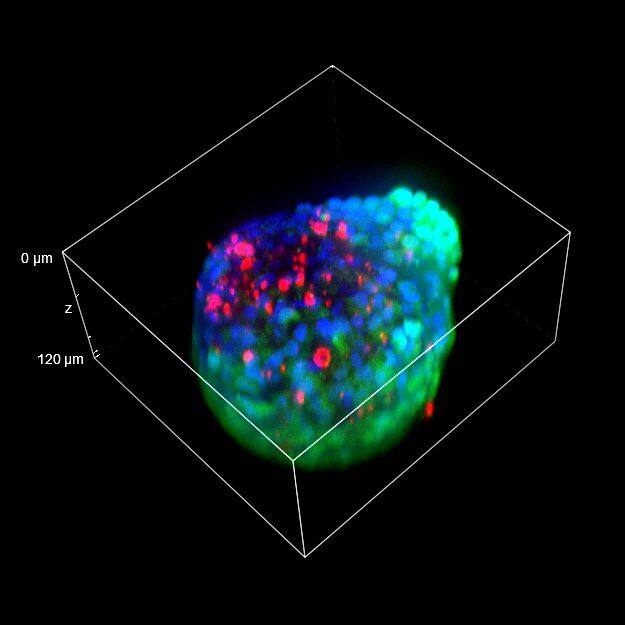

为了更好地理解 3D 细胞组织,在图 C 中,我们展示了使用两种物镜获得的同一球体的体积视图(120 um 厚),甚至在 3D 肿瘤球体的更深区域也能看到染色。最后,在 图 D 中,显示了使用 25 倍硅油物镜获得的整个球体的 3D 电影特效。

图 C:使用 20 倍空气物镜(左)和 25 倍硅油物镜(右)获得的球体的 3D 体积视图。活细胞用钙黄绿素(绿色)标记,死细胞用 PI(红色)标记。细胞核用 Hoechst(蓝色)染色。沿 Z 轴的比例尺:120 um。这些图像是使用 CrestOptics X-Light V3 转盘获取的。